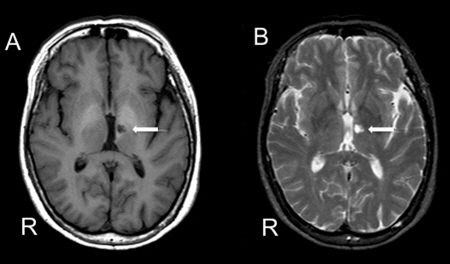

2) 열공성 뇌경색

열공성 뇌경색 MRI 뇌의 깊은 부위에 생기는 0.5~15㎜의 경색성 병소로 구멍을 형성하고 있는 것을 열공(lacuna)이라고 합니다. 고령층에 많으며 고혈압에 의한 뇌의 세동맥 경화가 관련된 것으로 알려져 있습니다.보통은 증상이 없지만 부위가 나쁘거나 여러 개 있으면 다양한 증상을 보일 수 있습니다. 예를 들어 거짓 연수 마비, 사지 경직, 종종 걷기, 지능 저하, 정동 장애(무리웃음, 무리울음) 등이 나타납니다.